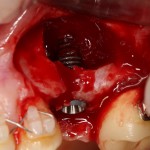

К установке имплантов можно приступать через 3-4 месяца (рис 52, 53):

Рисунок 52, 53. Установка импланта через 3 месяца после удаления зуба и синуслифтинга: слева – скелетирование верхней челюсти, справа – установленный имплантат.